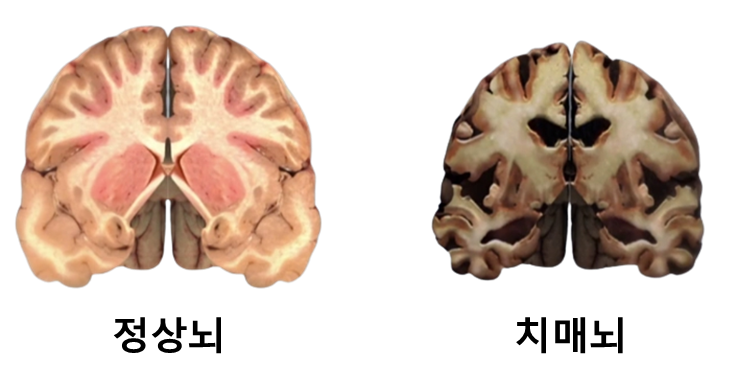

일반 노인성 치매보다 초로기 치매는 발병 후 뇌세포의 손상 속도가 빠르다는 것이 가장 큰 문제다.

이렇게 급속도로 진행되다보니 노인성 치매보다 공격적이고 위험하다.

치매에 노출되는 뇌를 살펴보면 독성물질인 뇌 조직 손상 단백질이 많이 발견된다.